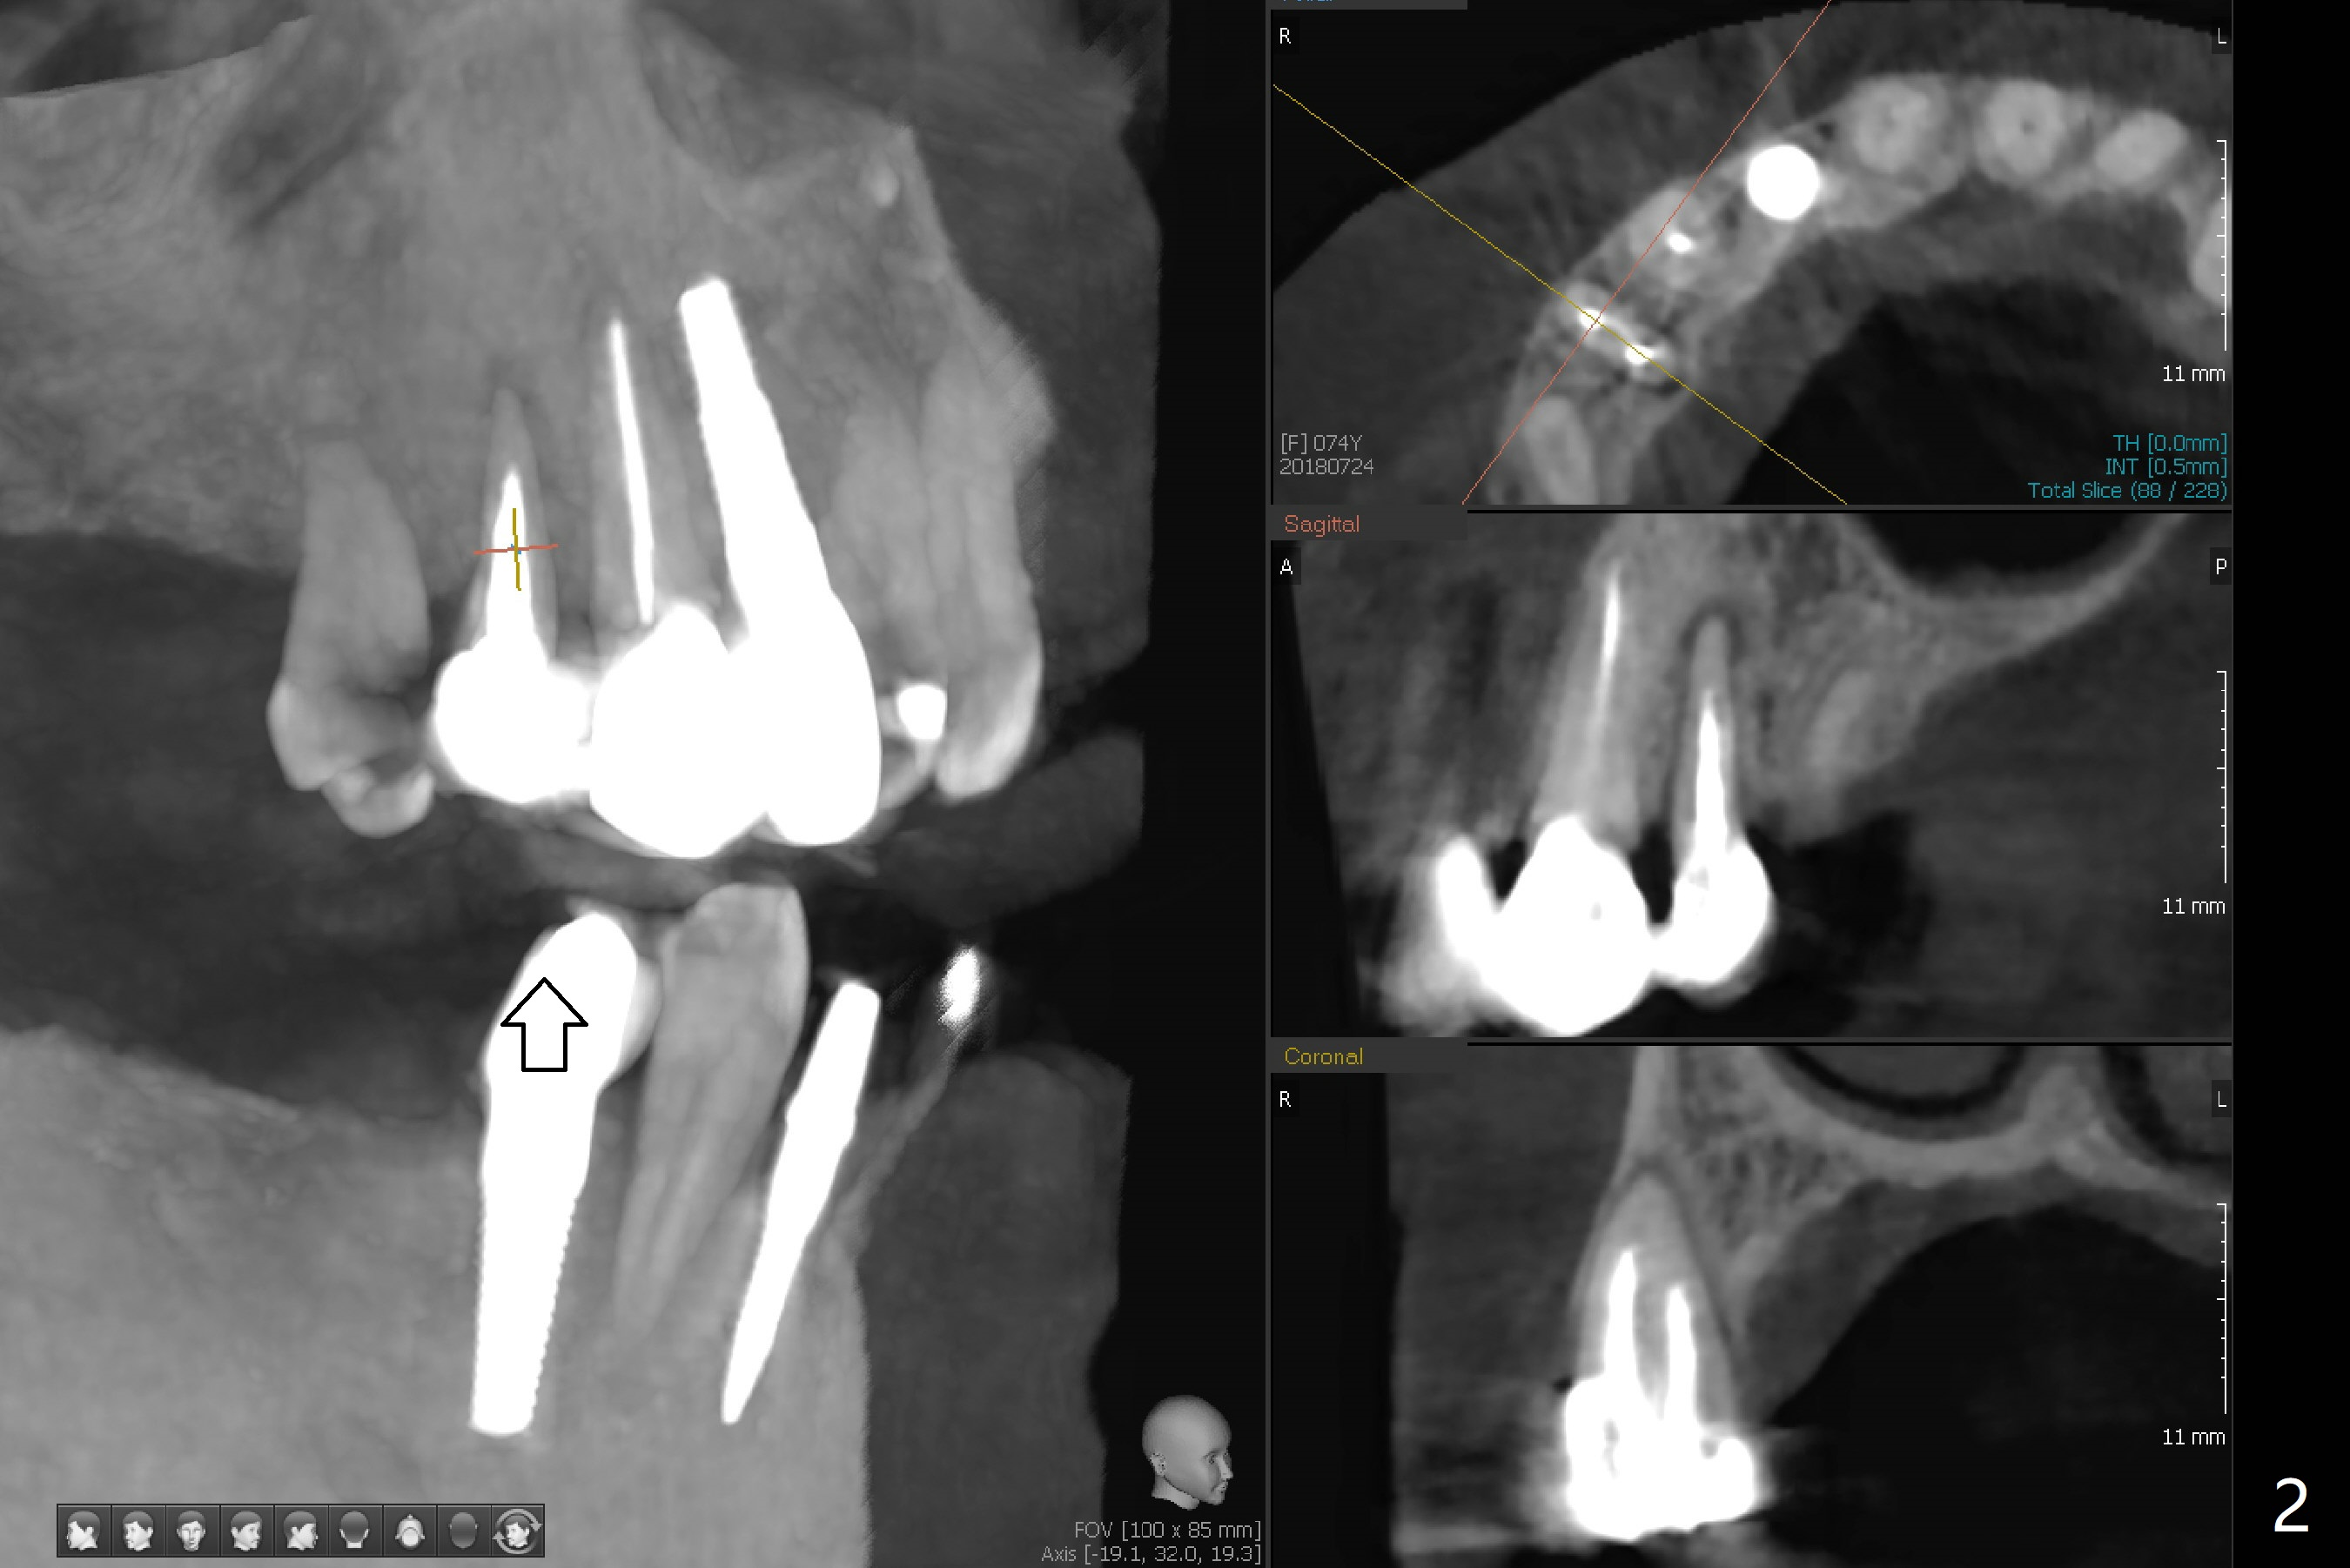

A 74-year-old woman requests treatment for a loose, tender tooth in the upper right quadrant (Fig.1). It may be due to occlusal trauma from the opposing implant tooth (Fig.2 arrow) and endo failure (Fig.2 coronal section). Because of history of low bone density and buccal placement at #7 with low primary stability, a small diameter implant will be placed palatally at #5. Either a 4x13 mm bone-level (Fig.3) or 4x17 mm tissue-level implant will be placed.